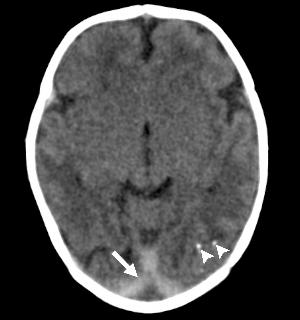

Intracranial calcifications were present in almost all of the neonates, most commonly found at the gray-white junction of the brain. All of the babies exhibited reduced tissue volume in their brains. All patients showed varying abnormalities in cortical development.

"The severity of the cortical malformation and associated tissue changes, and the localization of the calcifications at the grey-white matter junction were the most surprising findings in our research," Dr. Tovar-Moll said.

Figure 2. (a) Axial, (b) sagittal, and (c) coronal fetal T2-weighted MR images were obtained in a 29-year-old woman with confirmed Zika virus infection, initially seen for characteristic rash at 12 weeks of gestational age. (d) Axial postnatal CT image and (e–g) axial and (h) coronal T2-weighted MR images were obtained in her male neonate. The fetal MR images obtained at 34 weeks (a–c) show asymmetrical ventriculomegaly with a septation in the right occipital horn (arrowhead on a), small frontal lobes, thinning of the occipital parenchyma (left worse than right), underdeveloped sylvian fissures, and regions of thickened cortex, as in the right frontal lobe, which is suggestive of polymicrogyria (arrow on a). There is abnormal, increased signal intensity in the white matter. The postnatal CT image (d) obtained in the 22-day-old neonate shows punctate calcifications at the gray matter–white matter junction and asymmetrical ventriculomegaly. The T2-weighted MR images obtained at 26 days (e–h) show septation in the ventricle (arrowhead on e). Note how the right ventricle has relatively decreased in size compared with the prenatal image, whereas the left ventricle has increased in size. Under-rotation of the hippocampus (arrowheads on f) is demonstrated. There is clear asymmetry of the gyral pattern on g, which is relatively smooth in the left occipital region, with abnormal folds in the right occipital and frontoparietal regions (arrows on g). Subependymal cysts are visualized on h, which are not seen on fetal MR images.